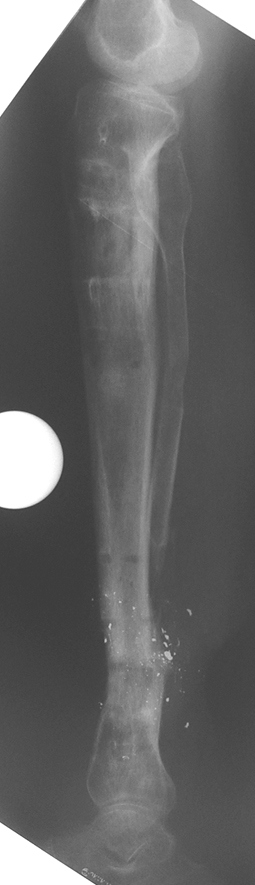

Travma Sonrası Bacak

Vaka 2